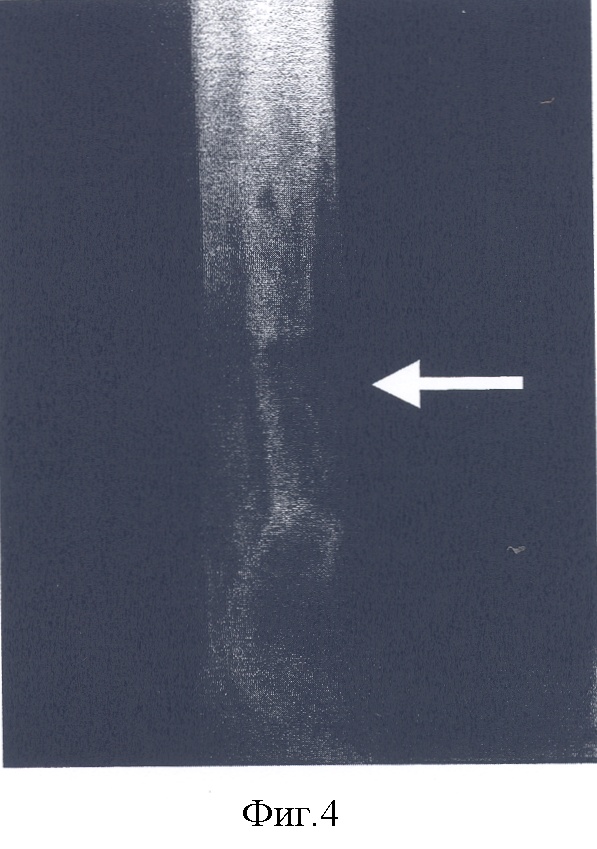

– на фиг.4 – рентгенограмма правой голени и стопы после остеотомии и удлинения большеберцовой кости для пластики таранной и пяточной костей; стрелкой показан костный регенерат;